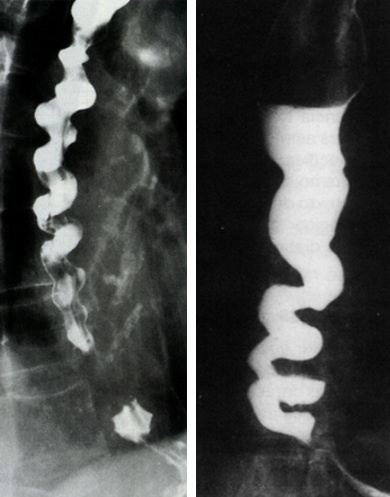

Esôfago esofagiano difuso

Esofagografia baritada (Saca rolhas/contas de rosário) e Esofagomanometria

Como está a esofagomanometria no Espasmo esofagiano difuso?

Contrações simultâneas, prolongadas, não propulsivas, > 120mmHg